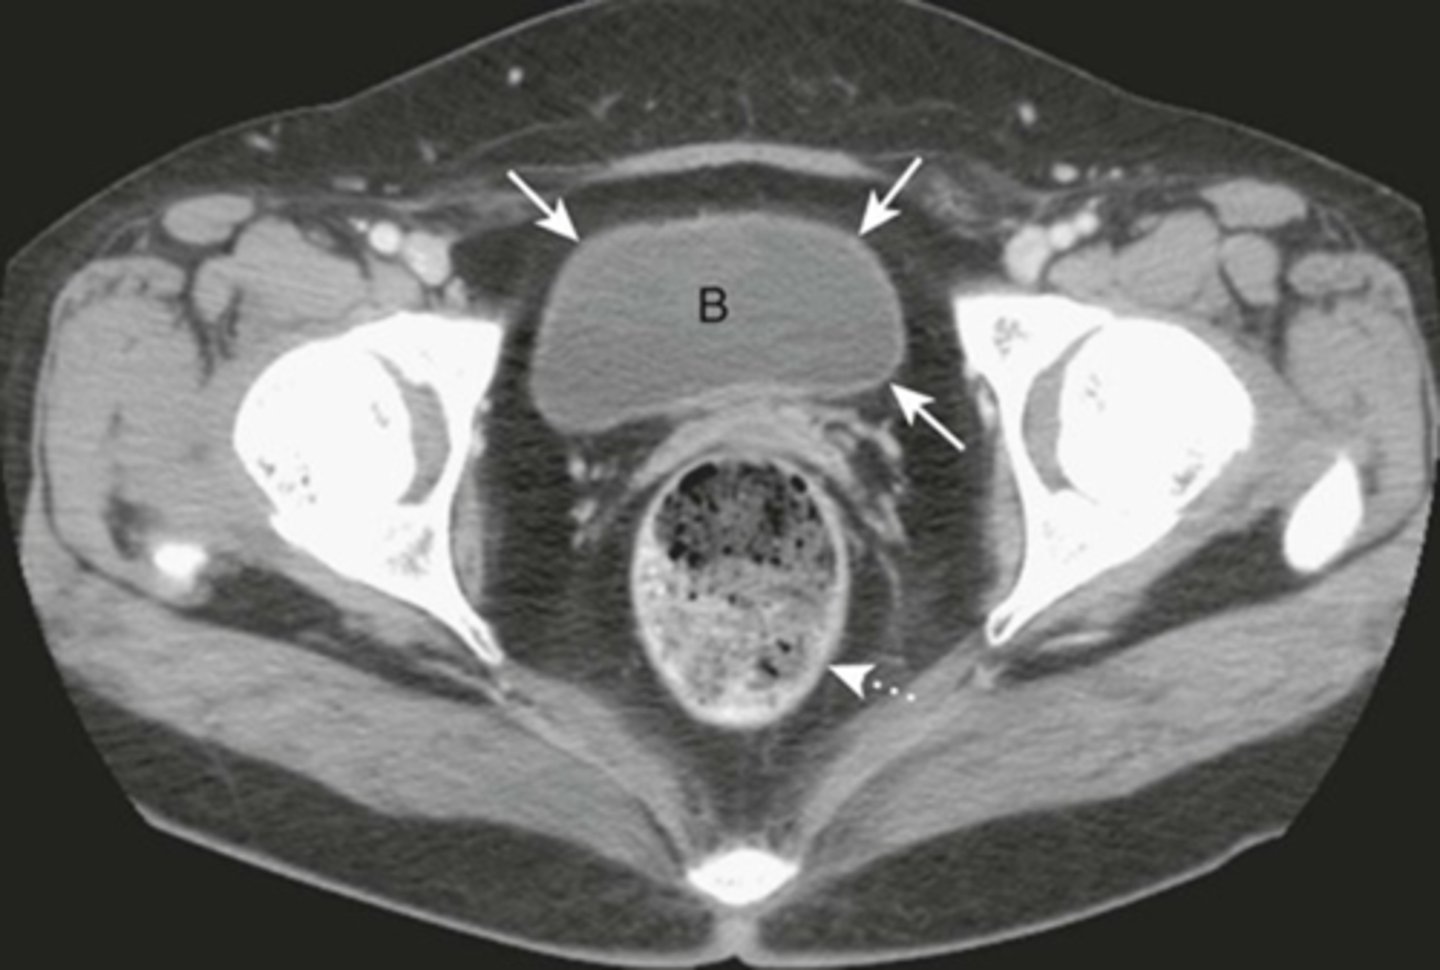

Normal bladder

B: unopacified urine in CT with IC contrast.

SOLID WHITE ARROWS: bladder wall, thin and equal thickness around the circumference of the bladder.

DOTTED WHITE ARROW: Rectum, lies posterior to bladder